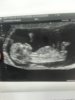

jakie piekne ♥No to przedstawiam moje maleństwo,zdrowiutkiepłeć nadal nieznana

termin przesunięty na 29.07